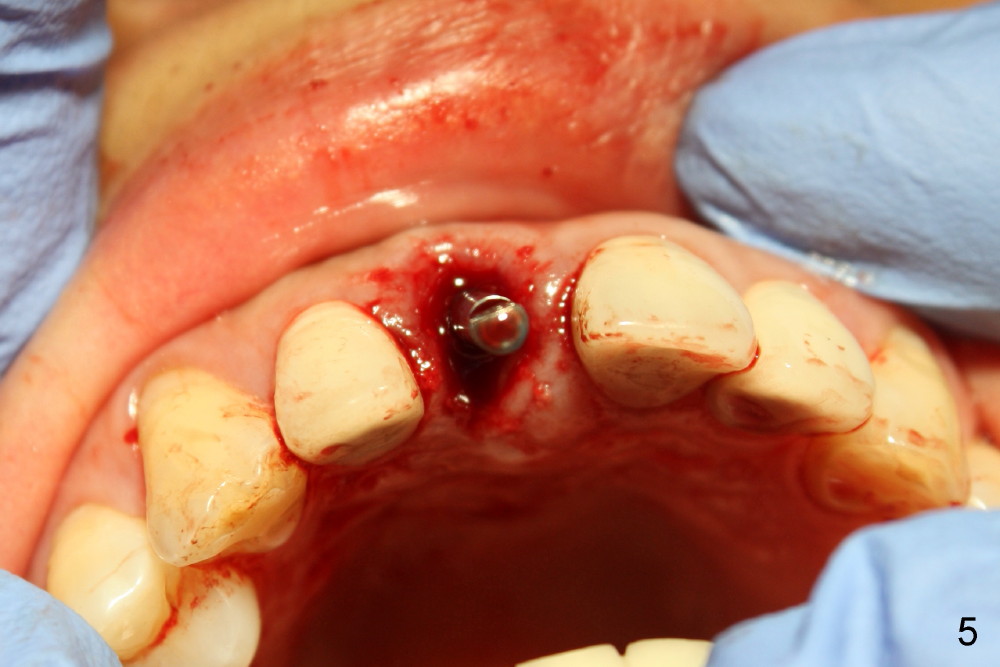

四十四岁女病人上颌中切牙突然断裂(图一:8),经过讨论,她同意植牙。由于根尖(图二黑线轮廓)上方骨头很多(箭头:鼻底),适合立刻植牙。牙根长度十一毫米左右,宽度约五毫米,准备植入直径五毫米植牙。拔牙后使用两毫米钻头,深度二十毫米(图三从颊侧牙龈缘算起),超过牙槽窝底部接近七毫米,所以植牙至少有七毫米新骨支持,将非常稳定。然后逐步使用2.5, 3.0, 和3.5毫米钻头,同一个深度,边钻边注意钻头(图四:D)近远中(图四)以及颊舌侧(图五)方向。